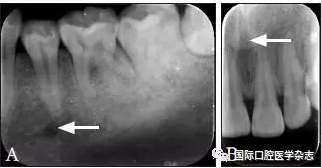

因拍攝角度的不同,頦孔和切牙孔影像可能與根尖重疊(圖8),應(yīng)注意觀察牙根的牙周膜及骨硬板是否連續(xù),或重新偏角拍攝X線片以確認其與牙根的關(guān)系。

圖 8 頦孔(A)和切牙孔(B)

Fig 8 Mental foramen(A) andincisive foramen(B)